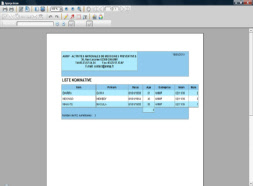

Un DVD regroupant les clichés numériques au format DICOM triés par ordre alphabétique vous est adressé.

Une liste de documents administratifs vous est fournie et vous évite un lourd travail de secrétariat: liste alphabétique des personnes ayant passées une radiographie au format Word, Excel, Pdf, HTML avec clichés au format JPEG, étiquetage informatisé des radios.

Dans le cadre de cette prestation un compte rendu papier reprend le compte rendu ou la synthèse des lectures effectuées par les pneumologues. Les anomalies recensées sont classées par ordre de priorité de suivi médical selon une codification interne.

La codification adoptée peut être délivrée au format BIT.